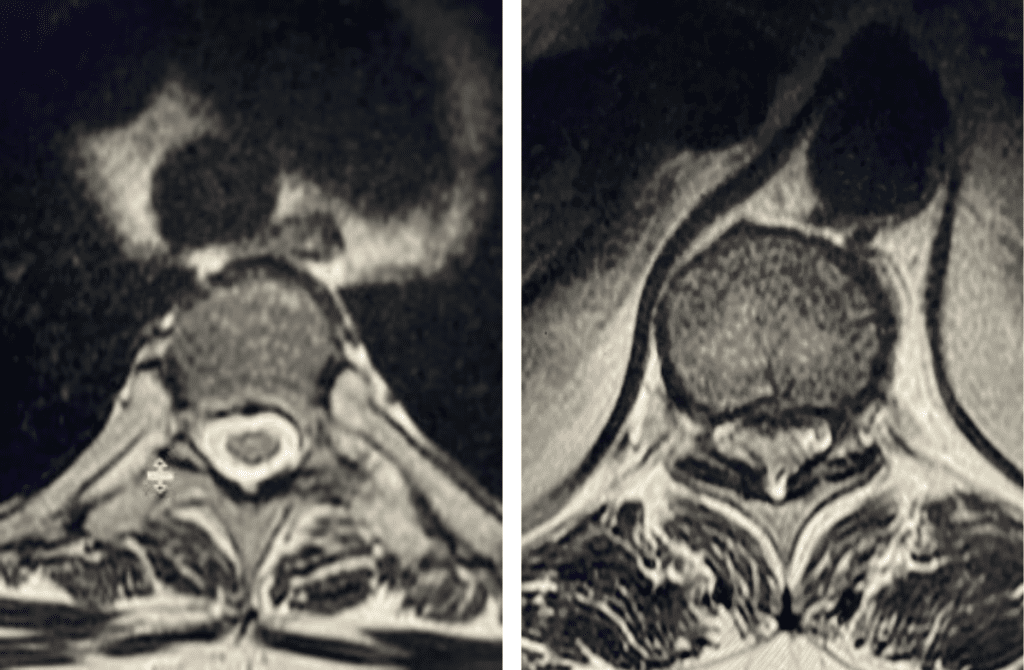

Thoracic stenosis is far less common than lumbar stenosis. Whereas the symptoms of lumbar stenosis are usually well-defined, thoracic stenosis can act like a great mimicker, […]

Nervous tissue is soft. The thecal sac is surrounded by a rigid bony ring which forms the spinal canal. Any mass that fills the very small […]